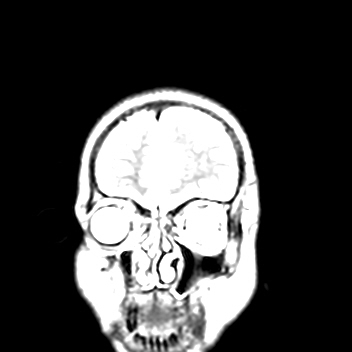

39 years old man with chronic alcoholic since 17 years.

& cough with cold & dark colour stool.

Now feeling weakness & dimness of vision.

O/E images: